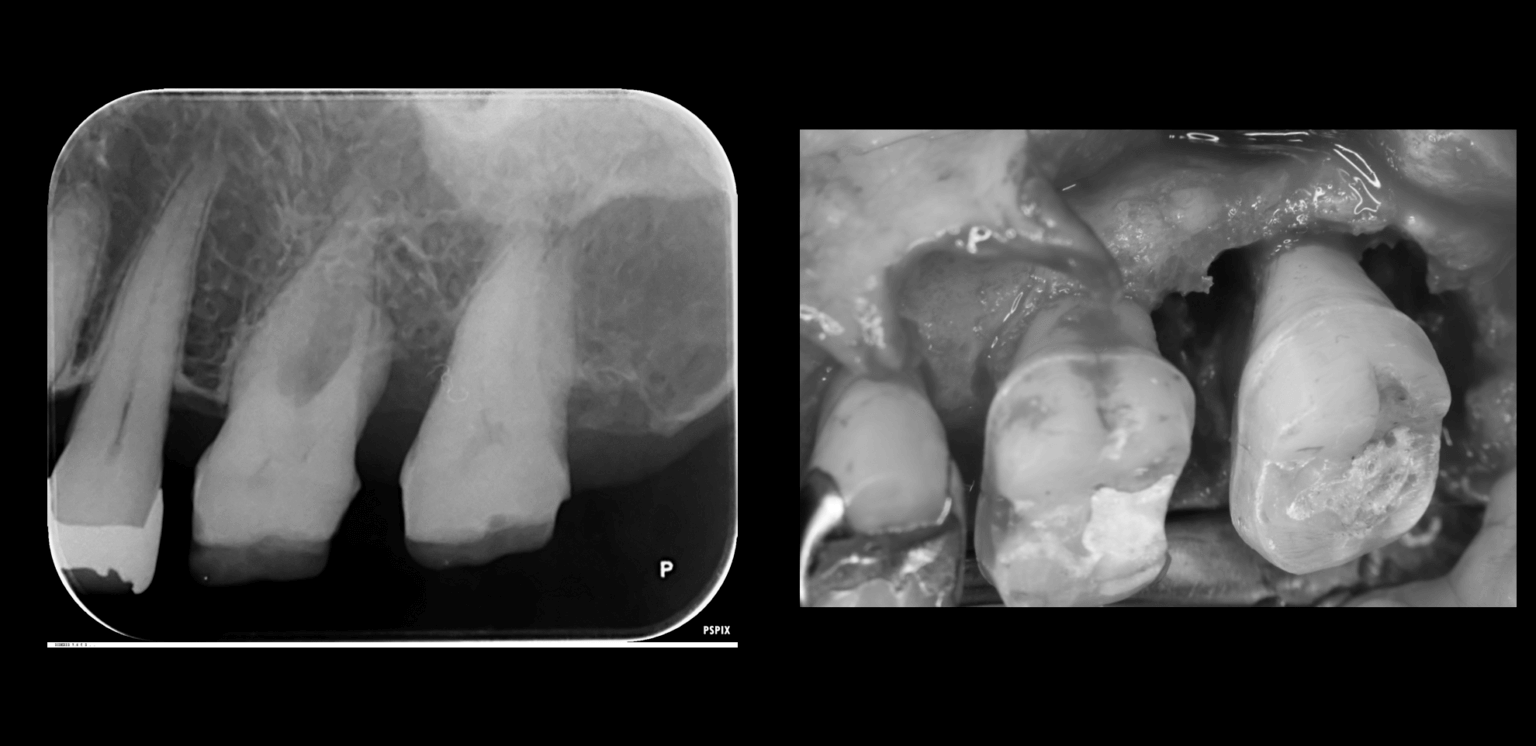

患者さんの経過